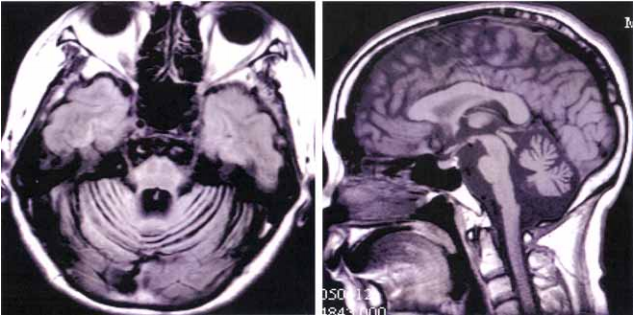

53 一位52 歲女性,最近數年來步態不穩,而且日趨嚴重,根據此2 張MRI 之T1WI 影像,最可能的診斷是:

(A) Multiple sclerosis(MS) (B) Olivopontocerebellar degeneration(OPCD) (C) Wallerian degeneration (D) Wallenberg syndrome